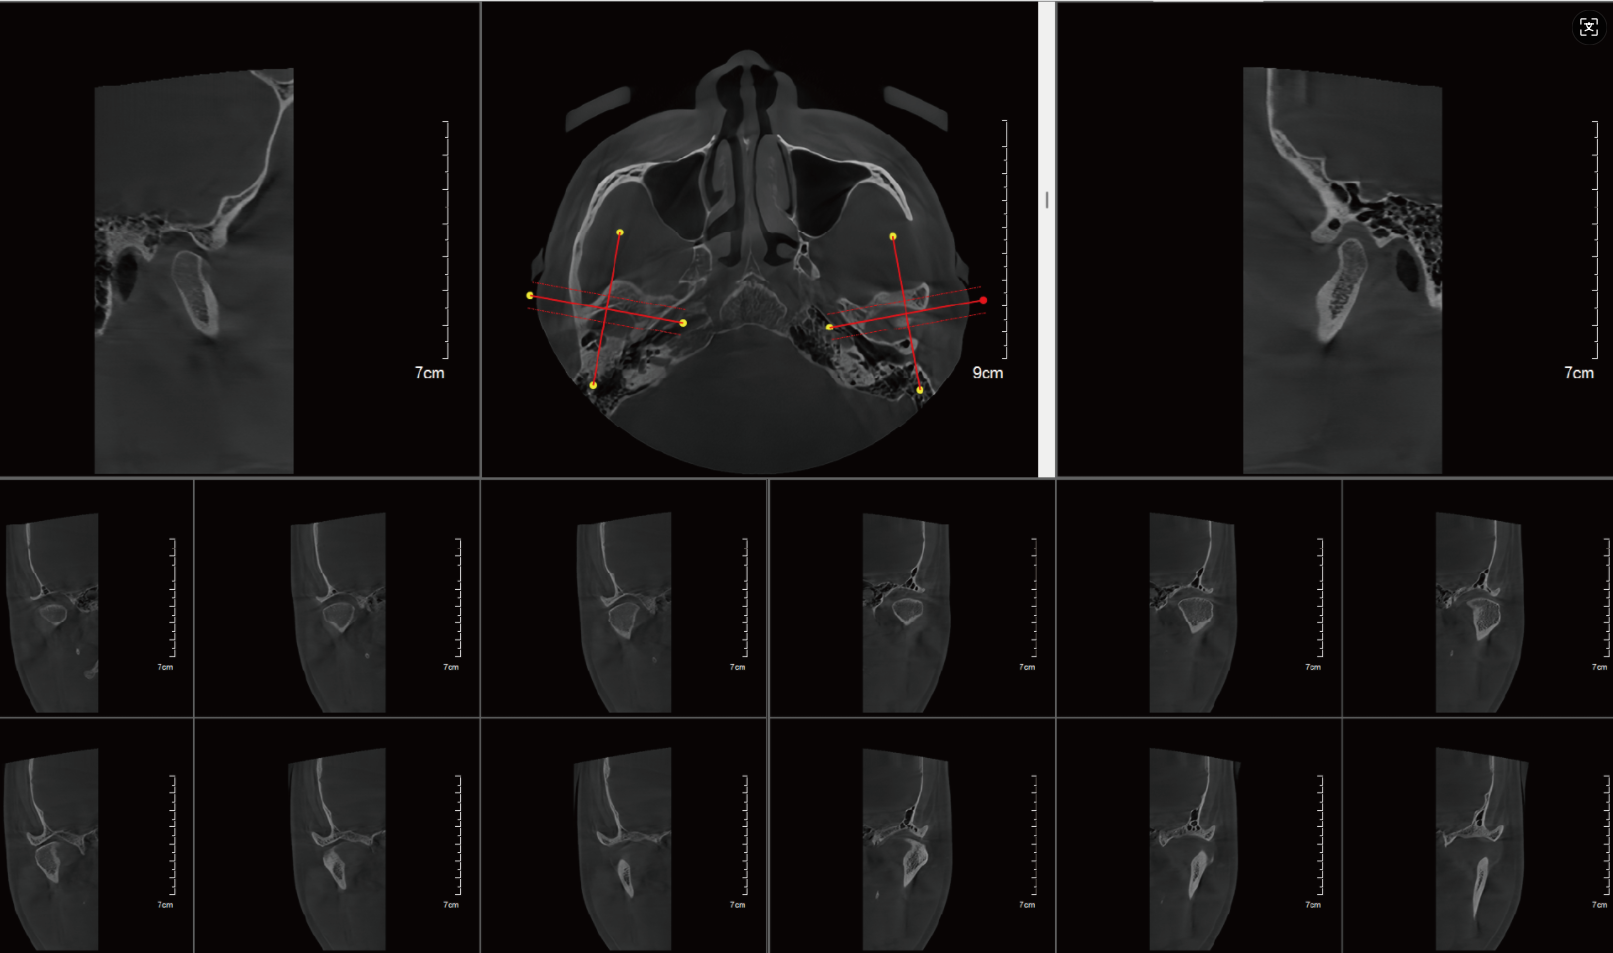

皓月CT自動(dòng)繪制神經(jīng)管、氣道分析

頜骨與顳下頜關(guān)節(jié)問(wèn)題:口腔CT能清晰顯示骨折線(xiàn)、關(guān)節(jié)結(jié)構(gòu)破壞、骨質(zhì)增生或吸收情況,對(duì)復(fù)雜頜骨骨折復(fù)位固定、關(guān)節(jié)疾病診斷至關(guān)重要。

皓月口腔CT自動(dòng)分析TMJ(顳下頜關(guān)節(jié))